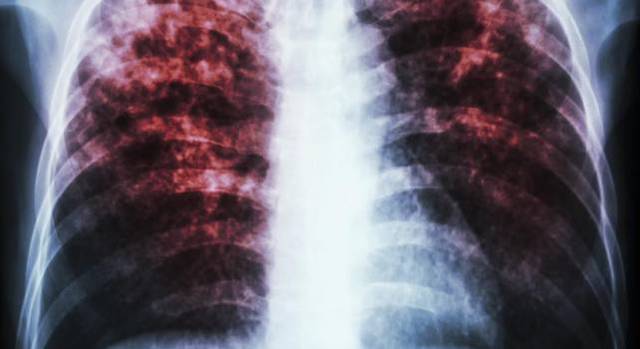

• Pierre Charles Alexander Louis, condujo gran cantidad de estudios demostrando tuberculosis no se transmitía hereditariamente y que la sangría era inútil.

Pierre Charles Alexander Louis, condujo gran cantidad de estudios demostrando tuberculosis no se transmitía hereditariamente y que la sangría era inútil.